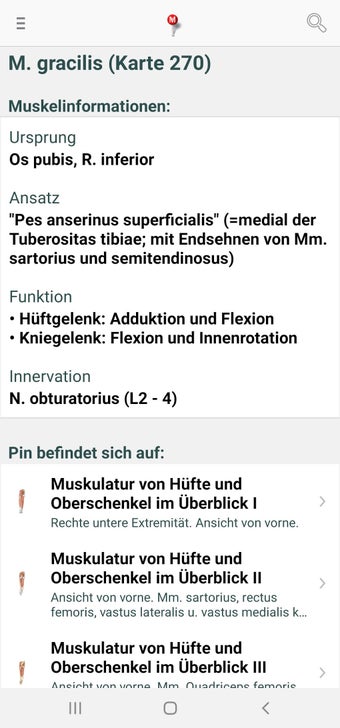

The app consists of different sections, each of which contains information about a specific part of the body. You will learn about the different organs, as well as the muscles, bones, and other important structures. You can test yourself with a unique quiz that consists of multiple-choice questions.

The app allows you to learn about the body in a simple and fun way, and to test yourself in a quick and easy way.